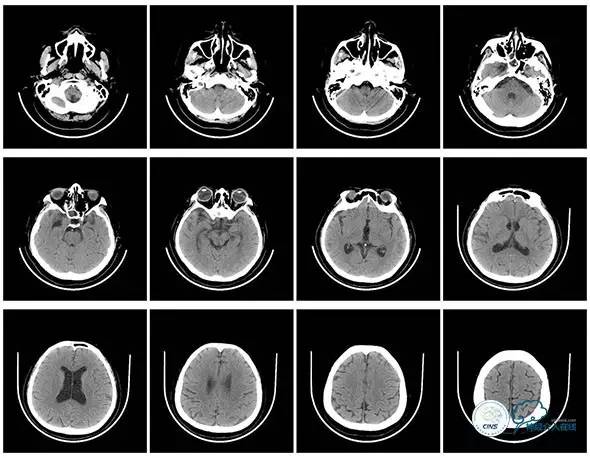

复查头颅及颞骨CT未见明显异常。

头颅CT(2017.6.20)

颞骨CT(2017.6.20)

术后头颅CT